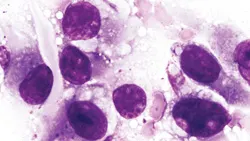

Figure 1. A neutrophil, two nucleated erythrocytes (metarubricytes), four polychromatophilic erythrocytes, and three abnormally shaped erythrocytes (arrows) in a blood film (Wright- Giemsa stain; original magnification, ´1000).

The regenerative anemia and slightly decreased total plasma protein concentration may be attributed to the ongoing hemorrhage present in this dog, but the presence of hyperbilirubinemia (slightly yellow plasma) and acanthocytes suggests that some component of erythrocyte destruction might also be present. The mild thrombocytopenia present was not sufficient to account for the persistent hemorrhage observed and no coagulation abnormalities were identified to explain the bleeding. Acanthocytes are spiculated erythrocytes with irregularly spaced, variably sized spicules (Figure 2, blue arrows). Acanthocytes have been recognized in animals with liver disease.1 They have also been reported in dogs with disorders that result in erythrocyte fragmentation such as hemangiosarcoma, disseminated intravascular coagulation, and glomerulonephritis.1-3 Lesser numbers of schistocytes (fragmented erythrocytes) were also present in blood from this dog (Figure 2, orange arrows).

Additional Test Results. Radiographs of the thorax revealed pleural thickening and pleural effusion. Radiographs of the abdomen were unremarkable. About 100 ml of blood was drained from the chest cavity by thoracentesis. Tissue was collected surgically from the right brachial plexus area. An anaplastic tumor involving spindle-shaped cells (sarcoma) was diagnosed from the stained impression smears (Figures 3 and 4). Given the history, physical findings, and laboratory findings, a diagnosis of hemangiosarcoma was made. The client elected euthanasia and granted permission for a cosmetic necropsy. A large thoracic mass was identified and removed for histopathologic examination. Histopathologic examination of the subcutaneous tissue and the thoracic mass confirmed the diagnosis of hemangiosarcoma.

Figure 3. Tissue imprint from surgical biopsy (Wright-Giemsa stain; original magnification, ´3000).

Figure 4. Tissue imprint from surgical biopsy (Wright-Giemsa stain; original magnification, ´ 1300).